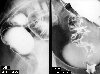

A case of juvnile polyposis of the large intestine with advanced rectal cancer.

Tokyo Pref., Cooperative study between National Cancer Center and Kyushu Cancer Center

Tumor-like lesions/Juvenile polyposis